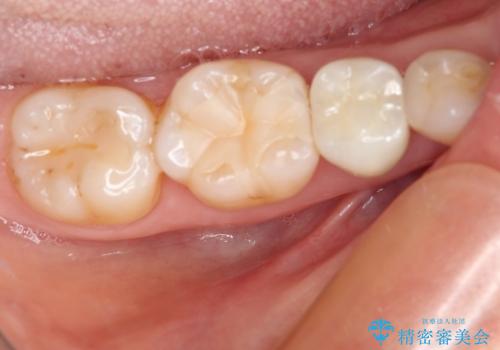

- 他院にて治療した詰め物が欠けてしまった事を主訴に来院された患者様です。

詰め物の範囲が大きく、部分的な詰め物では再び割れてしまうリスクが高いため、

オールセラミッククラウンにて補綴することとしました。

しみる症状はなくなり、見た目もきれいになり、とても満足されました。